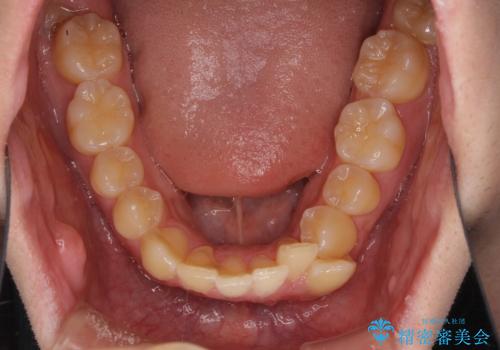

出っ歯と八重歯 目立たない裏側装置でスッキリとした口元に

- 上顎の前突感による口の閉じにくさと八重歯を気にして来院された患者様です。

目立たない装置を希望されたので、上顎が裏側装置のハーフリンガルを選択し、上下左右の小臼歯(計4歯)を抜歯して矯正治療を行うこととしました。

上下顎で左右差の大きい抜歯矯正を裏側装置で行ったため、非常に時間がかかりましたが、正中位置も良い位置に改善され、気になっていた突出感も解消されました。